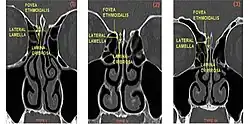

The Keros classification is a method of classifying the depth of the olfactory fossa.

The depth of the olfactory fossa is determined by the height of the lateral lamella of the cribriform plate. Keros in 1962, classified the depth into three categories.[3]

- type 1: has a depth of 1–3 mm (26.3% of population)

- type 2: has a depth of 4–7 mm (73.3% of population)

- type 3: has a depth of 8–16 mm (0.5% of population)

- type 4: has asymmetric depths (described by Stammberger)